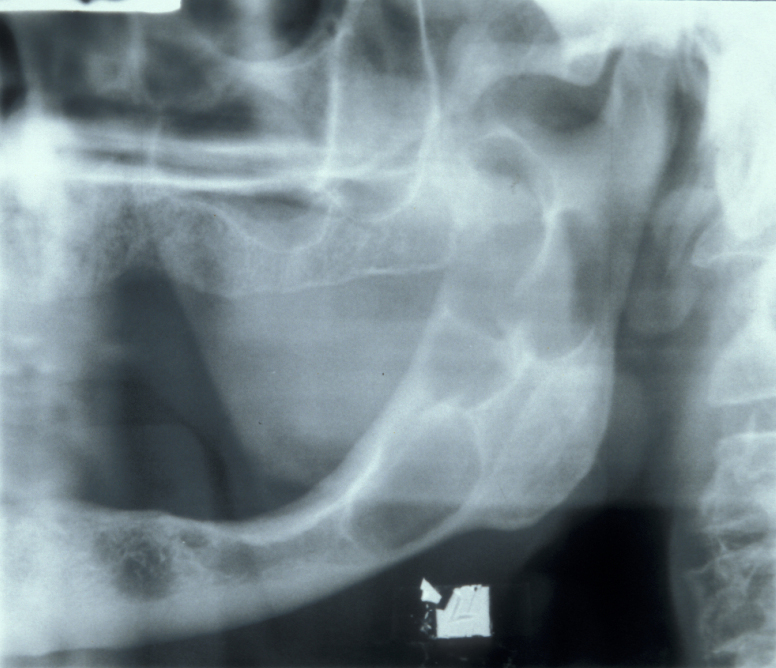

Radicular cyst – in a non-vital tooth, this cyst appears as a rounded periapical radiolucency in an X-ray radiograph, with loss of lamina dura (bone surrounding the tooth socket) and a sclerotic margin if it is a long-standing lesion. Figure 1 shows an example.